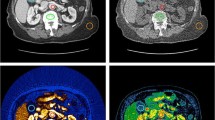

Kim KW, Lee JM, Klotz E, Park HS, Lee DH, Kim JY, et al. Quantitative CT color mapping of the arterial enhancement fraction of the liver to detect hepatocellular carcinoma. Radiology. 2009;250(2):425–34.

Ippolito D, Pecorelli A, Querques G, Drago SG, Maino C, Franzesi CT, et al. Dynamic computed tomography perfusion imaging: complementary diagnostic tool in hepatocellular carcinoma assessment from diagnosis to treatment follow-up. Acad Radiol. 2019;26(12):1675–85.

Borgheresi A, Gonzalez-Aguirre A, Brown KT, Getrajdman GI, Erinjeri JP, Covey A, et al. Does enhancement or perfusion on preprocedure CT predict outcomes after embolization of hepatocellular carcinoma? Acad Radiol. 2018;25(12):1588–94.